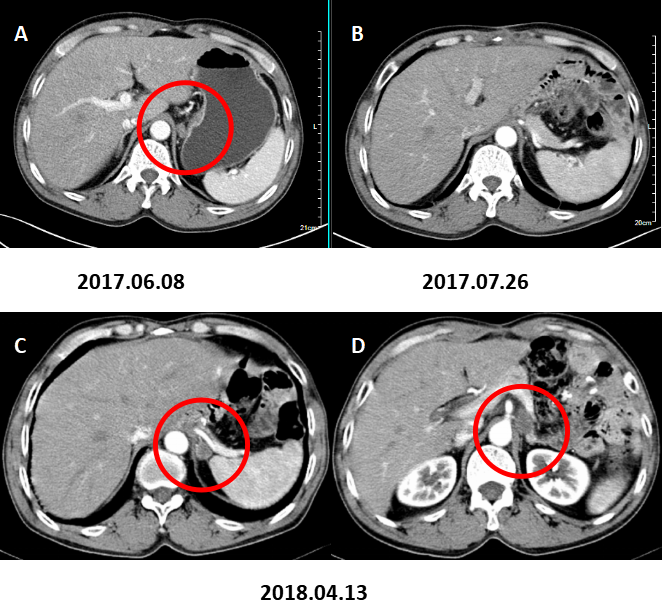

图5. 腹膜后淋巴结转移。

A:术前CT增强(2017.06.08)B:术后CT增强(2017.07.26)、C:术后CT增强(2018.04.13)示腹膜后小淋巴结。D:术后CT增强复查(2018.07.16)示腹膜后多发肿大淋巴结,转移考虑。

图6. 肝脏多发转移。

术前CT增强A(2017.06.08),术后CT增强B(2017.07.26)、C(2018.04.13)未见肝脏转移。D:术后CT增强复查(2018.07.16)示肝脏多发转移灶。

全腹部CT增强扫描(2018.11.03):前片所示肝内多发低密度灶未见明显显示。左侧肾上腺区及腹膜后多发肿大淋巴结,转移考虑,较前片增多增大。

图7. 肝脏转移灶基本消退。

A:术后CT增强(2018.07.16)示肝脏多发转移灶。B:术后CT增强(2018.11.03)示肝脏转移灶基本消退。

图8. 左肾上腺区,膈下及腹膜后淋巴结较前增大增多。

术后CT增强(2018.11.03)B1示左肾上腺区转移灶较前片(2018.07.16)。A1略增大;B2,B3示膈下及腹膜后淋巴结转移较A2,A3增大增多。